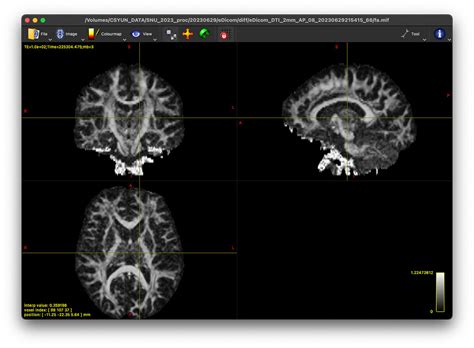

Once the diffusion tensor has been estimated, calculating FA becomes remarkably straightforward. The tensor2metric command in MRtrix3 allows for the extraction of various tensor-derived metrics, including FA. Simply specify the output file name and the desired metric (FA), and MRtrix3 will efficiently generate a map of FA values across your brain image. Additionally, it’s often beneficial to generate other related metrics such as mean diffusivity (MD), radial diffusivity (RD), and axial diffusivity (AD), which can provide complementary information about tissue microstructure. These can also be extracted using tensor2metric. Finally, visualizing the results is crucial for interpreting the calculated FA values. MRtrix3 integrates seamlessly with other neuroimaging software packages, enabling you to visualize your FA maps in three dimensions and overlay them onto anatomical images for precise anatomical localization. In conclusion, by meticulously following these steps and understanding the underlying principles, you can harness the power of MRtrix3 to accurately calculate FA and gain valuable insights into the intricate microstructural organization of the brain’s white matter pathways. Remember to consult the comprehensive MRtrix3 documentation for more detailed information and advanced options.

The resulting “tensor.mif” file contains the six unique elements of the diffusion tensor for each voxel. These represent the diffusion in three orthogonal directions and their interactions (off-diagonal elements). You can visualize these tensor images using tools like mrview, which can help you qualitatively assess the diffusion characteristics in different brain regions. However, for quantitative analysis and to obtain the FA, further processing steps are needed, which will be discussed in subsequent sections.

How do I visualize FA maps in MRtrix3?

MRtrix3 provides the mrview command for visualizing FA maps (and other derived metrics). mrview offers interactive 3D visualization, allowing you to explore the data in different views and planes. You can also overlay FA maps onto anatomical images for better anatomical context.